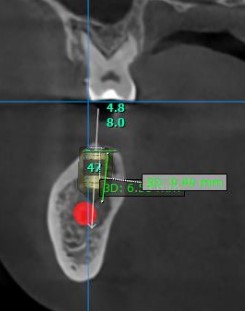

Good morning everyone, I would like to get your opinion on the following treatment options for this case. This patient has missing 47, 46 and a retained root at 45. Interocclusal space is about 5mm ( so i cannot perform vertical bone augmentation), bone height is limited, about 10mm ( close proximity to ID canal) and bone width is not satisfactory as well . I have not used any short implants with high engaging threads ( BLX implant) in my practice so I would like to get everyone’s input on this. Thank you.

Treatment plan 1 : 3 units straumann BLX implants ( 45 : 3.75mm x 6mm, 46 : 3.75mmx6mm, 47: 4.5mmx6mm) + GBR with autogenous and straumann xenograft + 3 units splinted final prosthesis

Treatment plan 3 units straumann BLT implant (45 : 4.1mm x 8mm, 46 : 4.1mmx8mm, 47: 4.8mmx8mm) + GBR with autogenous and straumann xenograft + 2 units splinted 46,47 and single unit 45 final prosthesis

– Concern – Longer implants but near to ID canal, about 1-2mm away if place implants at the same level at bone crest and limited/abscence of buccal bone

More lingual placement on 47 and site 45 looks very narrow so may have the most predictable outcome performing GBR in area prior to placement and I would go with shorter implants to allow more subcrestal placement which will also allow more restorative space. I also typically prefer individual implants but in this case an implant bridge may make more sense for the pt. And/or minimize treatment for patient as the middle site has the least bone width.

Thanks for the post William! I think in this case, you should plan a GBR like @restoredsmiles suggested. Also, the shorter implants are the way to go here so you still have 2mm safety zone before the nerve canal!